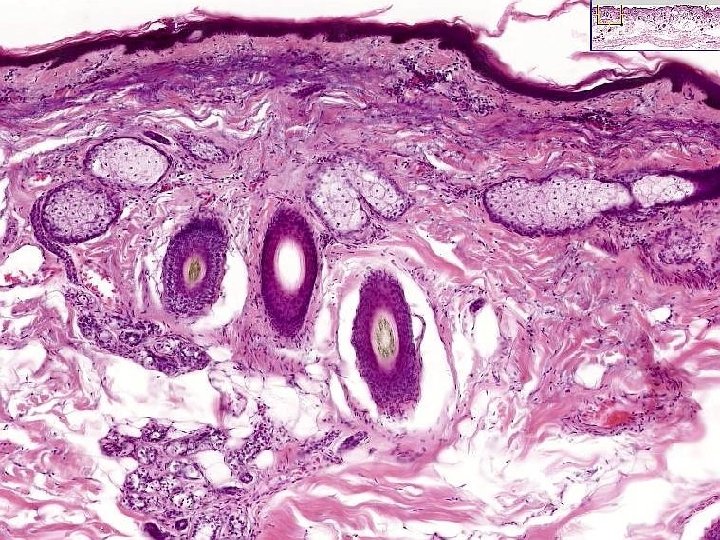

BENIGN Epidermal Tumors • • • Seborrheic Keratosis Acanthosis Nigricans Fibroepithelial Polyp (skin tag) Epidermal (inclusion) Cyst Adnexal tumors : Eccrine, Apocrine • Keratoacanthoma

ADNEXAL TUMORS • HAIR FOLLICLES • SEBACEOUS GLANDS • SWEAT GLANDS –ECCRINE –APOCRINE